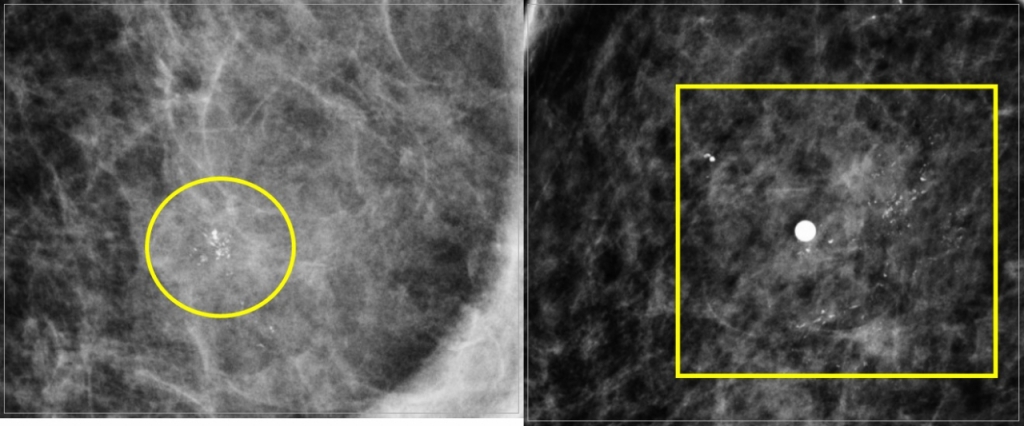

유방 석회화가 양성인지, 암과 같은 악성인지 확인하는 '기준'은 유방 석회화의 크기와 형태다. 암으로 인한 석회화는 '군집성 미세 석회화'라는 특징이 있기 때문이다. 이름처럼 한곳에 모인(군집성) 작은 크기의(미세) 석회로 X선 영상에서는 마치 하얀 가루가 한 곳에 뭉친 것처럼 보인다. 보통 0.5㎜ 미만의 미세 석회가 5개 이상 모여 있으면 군집성 미세 석회화로 본다. 안 교수는 "암으로 인한 미세 석회는 골형성 인자 등의 영향으로 유방 조직이 전체적으로 변형돼 생기는 석회화와 달리 암 주변에 모이는 특징을 띈다"며 "이때는 조직검사를 통해 악성(암) 인지 꼭 감별해야 한다"고 조언했다.

우리나라 여성은 유방 조직 중 유즙을 분비하는 유선이 상대적으로 많은 '치밀유방'이 많아 단순 유방 촬영술로는 석회화의 모양이 정확하게 확인되지 않을 수 있다. 이때는 특정 구역을 확대하는 '디지털 유방 확대 촬영술'을 추가로 시행해 석회화의 크기나 형태를 더욱 정확히 판단해야 한다. 모양이 좋지 않은 미세 석회는 유방촬영술을 시행하며 실시간으로 조직을 검사하는 '정위적 조직검사'를 시행하기도 한다.